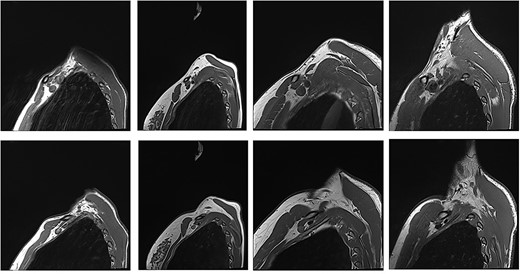

With the arm elevated, there is narrowing of the costoclavicular space between the posterior border of the clavicle and anterior border of the first rib (Figs 1 and 3). In unaffected patients, there is a small amount of fat that persists around the cords of the brachial plexus with the arm elevated (Fig. 2). In our series, we considered a patient to be positive for nTOS if there is loss of the perineural fat signal demonstrating that the nerves are in direct contact with the posterior border of the clavicle and anterior border of the first rib (Fig. 1b).

Panel a. Sagittal T1-weighted MRI of the costoclavicular space without imaging evidence of nTOS. Arm alongside the body (i) and arm elevated (ii). Maintenance of a fat plane surrounding the cords is seen with physiological narrowing of the space. Panel b. Sagittal T1-weighted MRI of the costoclavicular space with imaging evidence of nTOS. Arm alongside the body (i) and arm elevated (ii). Narrowing of the costoclavicular space and complete effacement of the fat indicating brachial plexus compression. Panel c. Venograms conducted with contrast injection in the antecubital vein while the arm is alongside (i) and in salute pose (ii) demonstrates tight stenosis of the subclavian vein and collateral flow. The MRI also showed effacement of the brachial plexus. The 36 year-old male subject had an excellent outcome after excision of the 1st rib. C: Clavicle; FR: First rib, SV: Subclavian vein, SA: Subclavian artery, LC: Lateral cord, MC: Medial cord, PC: Posterior cord.